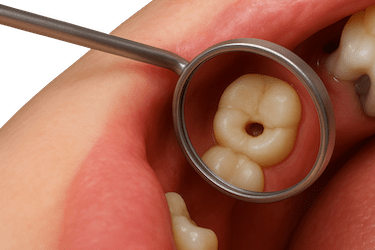

Las caries que avanzan hasta el interior del diente pueden llegar al nervio y causar una infección severa.

Con la endodoncia se elimina la pulpa dañada y se evita la extracción del diente.

El paciente puede presentar ganglios inflamados y hasta fiebre. El tratamiento de endodoncia es necesario cuando la cavidad o hueco del diente es muy profunda y llega al nervio.